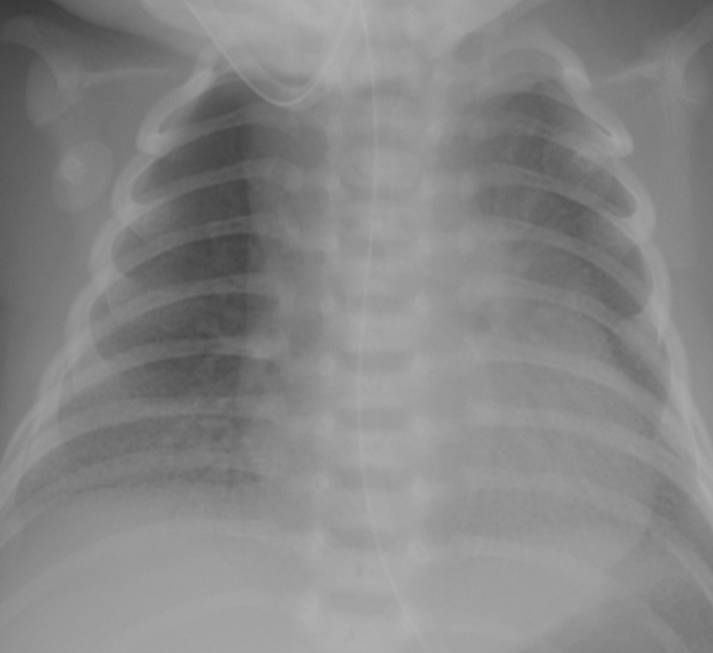

典型胸片結(jié)果:

(II-III級(jí)肺透明膜病變)